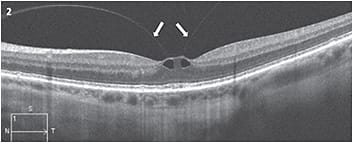

The IVTS defined VMA as vitreous attachment to the macula with adjacent separation of the vitreous from the retinal surface without distortion of the retinal anatomy1 (Figure 1). VMT is defined as VMA with resultant distortion of the retinal architecture, which can include intraretinal cysts, distortion of the foveal anatomy or focal neurosensory foveal detachment (Figure 2). VMA and VMT can either be focal (1,500 µm or smaller) or broad (larger than 1,500 µm).

Figure 2: OCT shows focal VMT with intraretinal cysts; arrows highlight the posterior vitreous cortex.